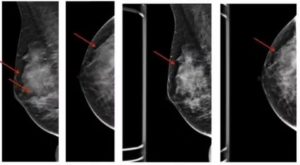

Диагностирование подразумевает посещение пациенткой маммолога, проведение маммографии молочной железы, ключичных и подмышечных областей (на 5–7 день после начала менструального цикла).

При маммографическом исследовании наблюдаются овальные участки уплотнений, имеющие нечеткие контуры. Такая форма называется диффузной, при ее наличии преобладают фиброзные, желестые или кистозные компоненты (много кист), различают также мастопатию фкм смешанной формы, и называется она фиброзно-кистозная болезнь.

Данная форма болезни четко выражена, а потому в ряде случаев определяется при помощи пальпации, в том числе при самообследовании женщины. Не стоит пренебрегать и современными методами диагностики — УЗИ, маммографией — ведь только они определят характер болезни и с предельной точностью укажут ее локализацию и масштабы.

При самостоятельном ощупывании границы разросшейся ткани определить бывает сложно, для этого требуется пройти маммографию.